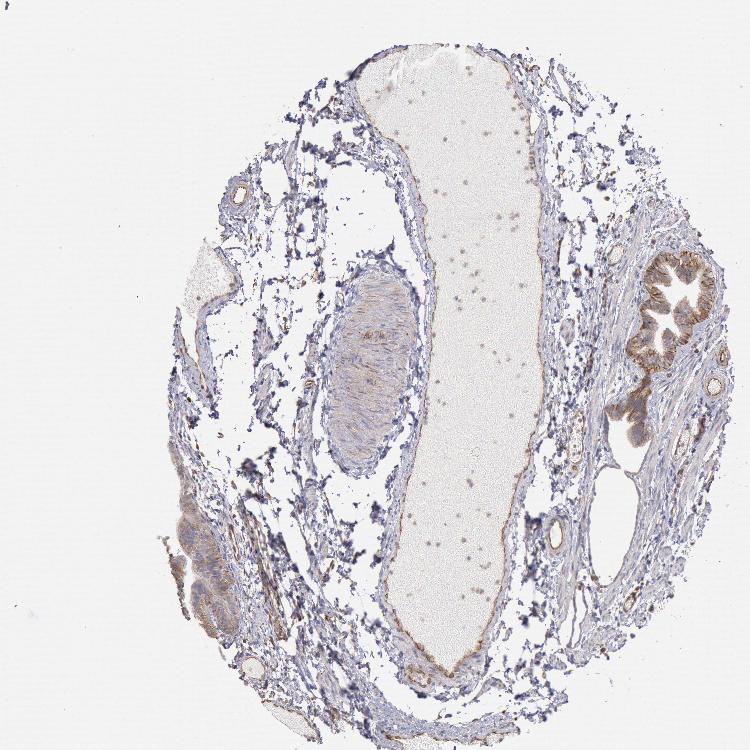

RNF139